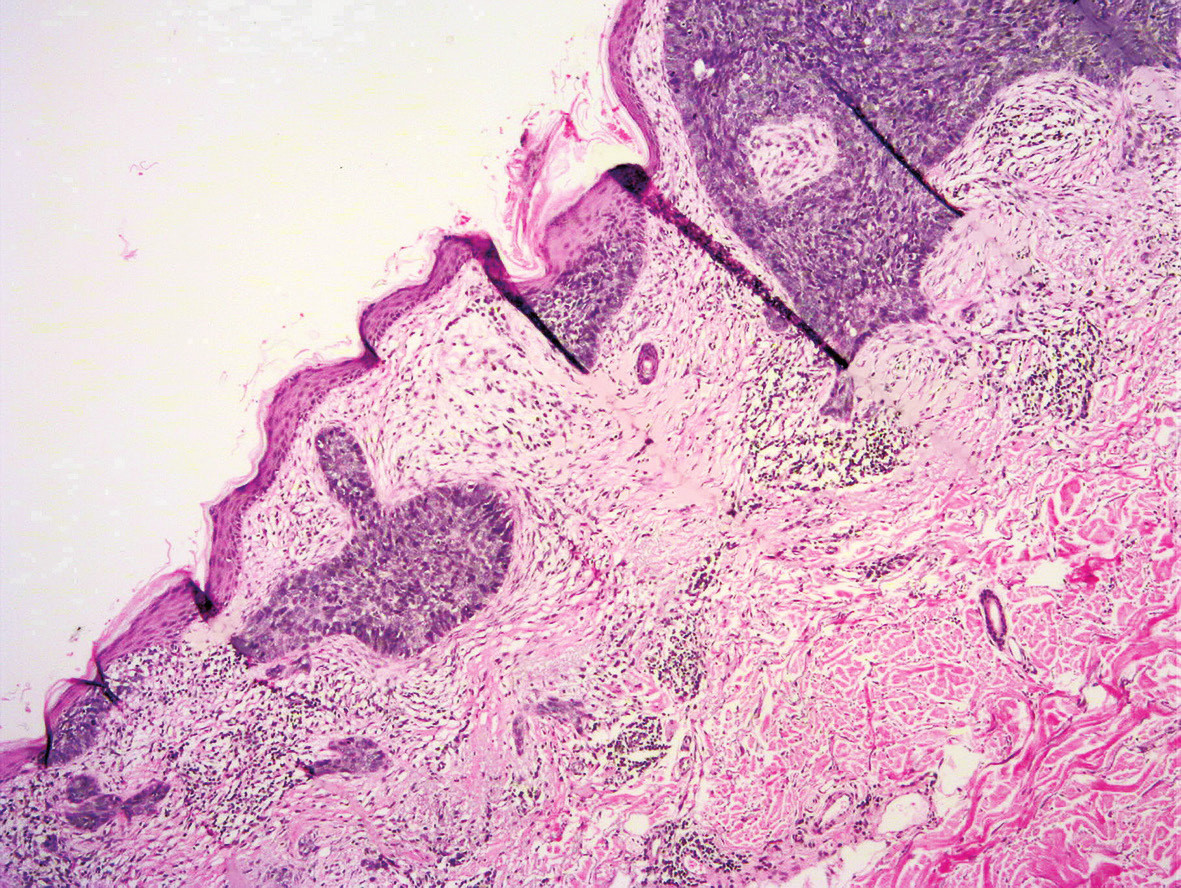

Micronodular variant of basal cell carcinoma, with small nests of Basal Cell Carcinoma Nodular And Micronodular Types There are four main types of basal cell carcinoma (bcc), including: What are the types of basal cell carcinoma? Types of basal cell carcinoma. There are several distinct clinical types of bcc, and over 20 histological growth patterns of bcc. This type is similar to nodular bcc but with smaller nodules. It’s often found on the back as light yellowish. Basal Cell Carcinoma Nodular And Micronodular Types.

Micronodular basal cell carcinoma MyPathologyReport.ca Basal Cell Carcinoma Nodular And Micronodular Types Which treatment is best for you depends on the type, location and size of your cancer, as well as your preferences and ability. Types of basal cell carcinoma. This type is similar to nodular bcc but with smaller nodules. Clinically found elevated or flat infiltrated tumors. Most common type of facial bcc; It’s often found on the back as light. Basal Cell Carcinoma Nodular And Micronodular Types.